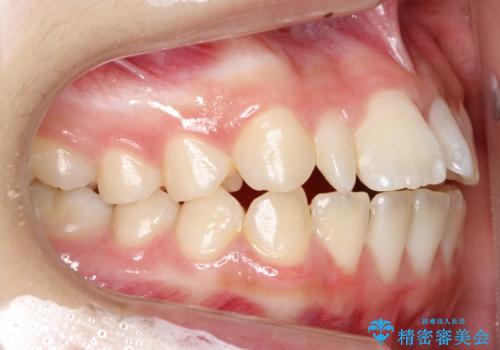

上あごの2番目の歯は矮小歯といって、生まれつき小さい歯となる事がよくあります。

このような場合、矯正によりスペースを集め、本来あるべき形態にセラミックで修正することもできます。